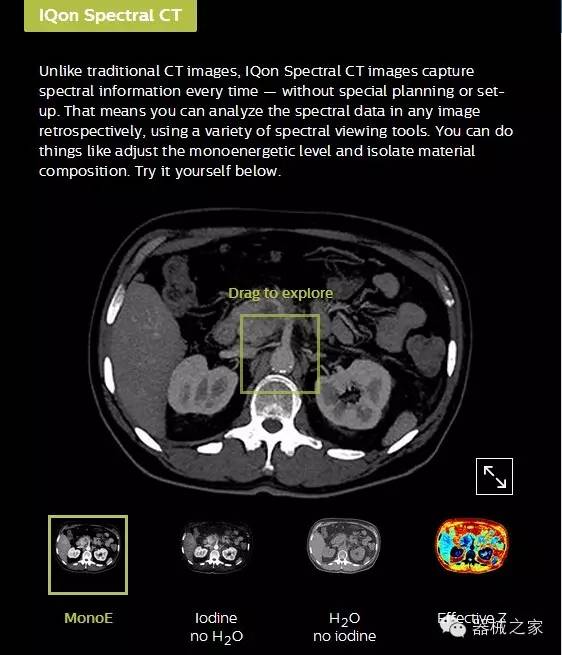

IQon光譜CT能夠按照需求提供光譜量化和工具,并能通過簡單工作流程、在低劑量下對結構進行定性分析

IQon光譜CT -- 是業(yè)界首臺以探測器為成像基礎的光譜CT,它可以在單次常規(guī)掃描下獲得傳統解剖影像及光譜功能影像。不僅可以提供精準的診斷信息,還可簡化工作流程、在低劑量下完成定量與定性分析。